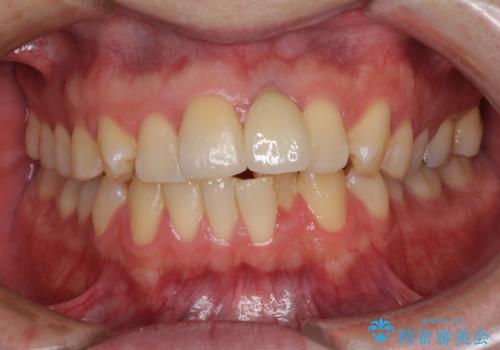

インプラントが唇側に埋入されており、セラミッククラウンの歯肉ラインが左右非対称となっていました。

仮歯は両サイドの歯と接着剤で止められており、接着が著しく変色していたため、セラミッククラウンが装着されて自然な口元となりました。